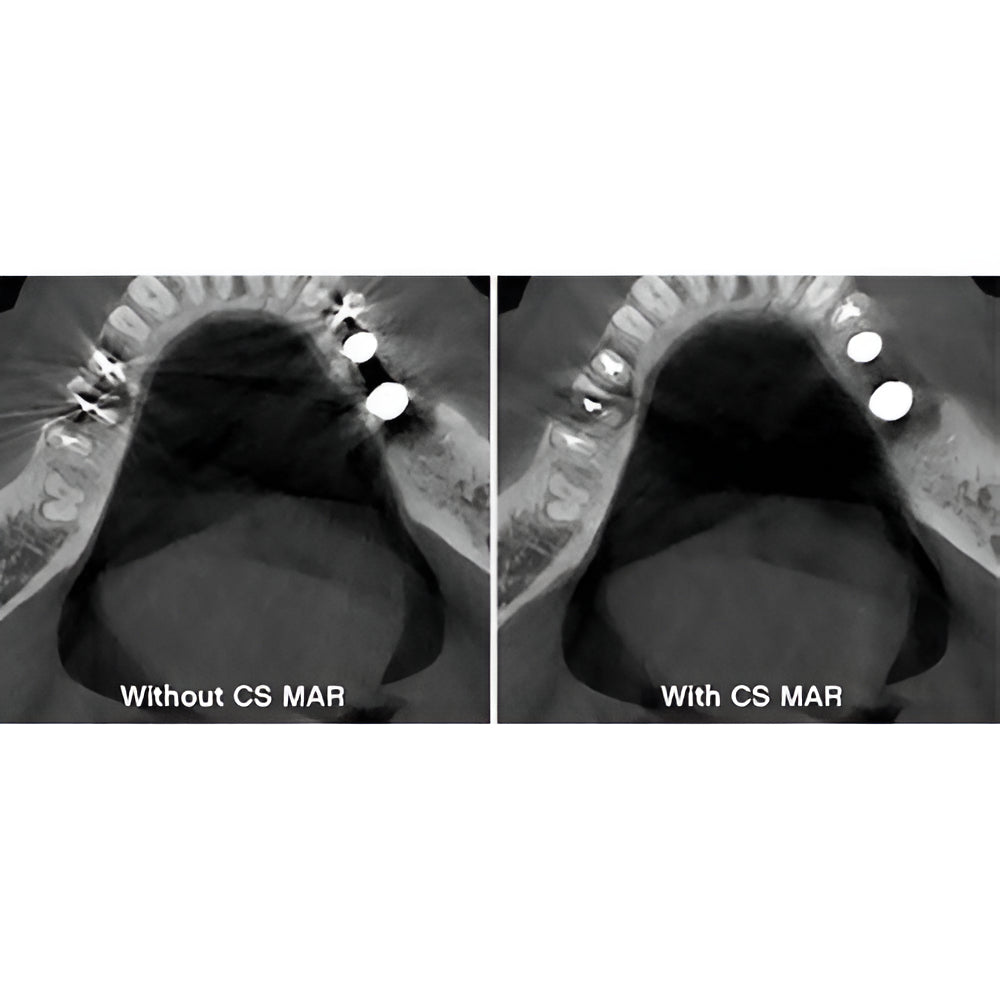

Enter a world of crystal-clear 3D images with the CS 8200 3D Access-a CBCT system that’s state-of-the-art, but intuitive and easy to use, taking your dental practice to the next level. Enjoy CBCT imaging that’s easier than you think and built on an open platform so that you can activate your future practice here and now.

- Easy, advanced CBCT imaging now available to everyone

- Versatile 4-in-1 solution ideal to expand treatment options